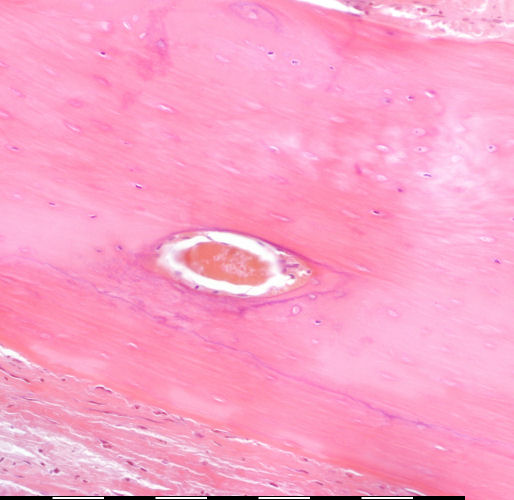

back Medium magnification of immature bone